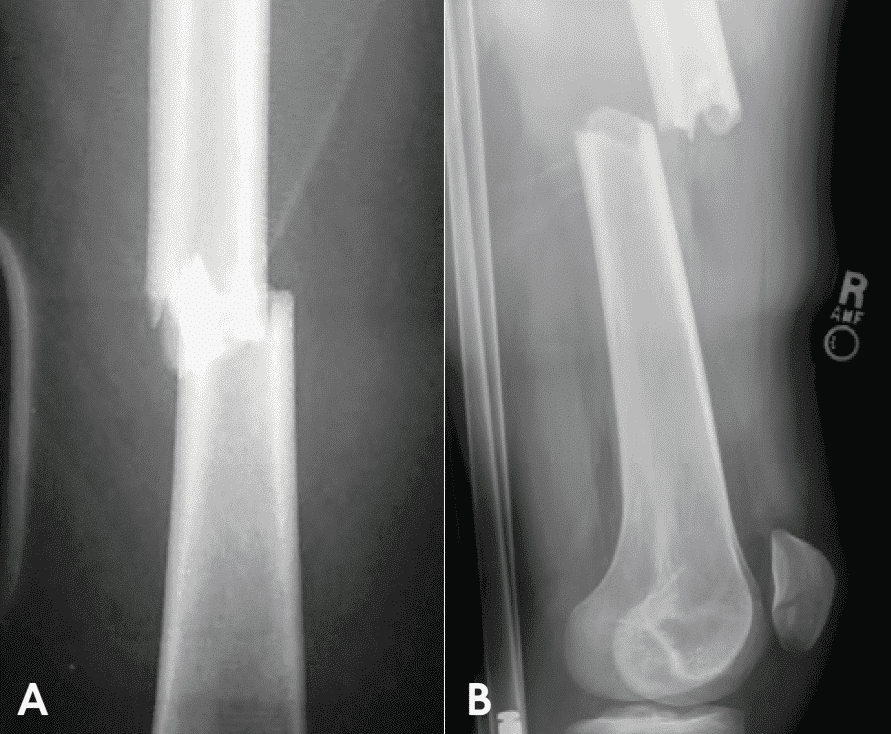

Рентгенограма, зроблена під правильним кутом, підтверджує анамнез і результати медичного огляду (зобр. 8.9). Залежно від гемодинамічного стану пацієнта рентгенологічне обстеження, можливо, доведеться відкласти, поки стан пацієнта не стабілізується. Треба також зробити рентгенограми суглобів над і під місцем можливого перелому з метою виключення можливості прихованих вивихів і супутніх ушкоджень.

A. Дистальний відділ стегнової кістки у прямій проєкції.

B. Дистальний відділ стегнової кістки у бічній проєкції.

Рентгенографію ушкоджених довгих трубчастих кісток потрібно виконувати у двох ортогональних проєкціях, необхідна візуалізація усієї кістки. Одного знімка недостатньо